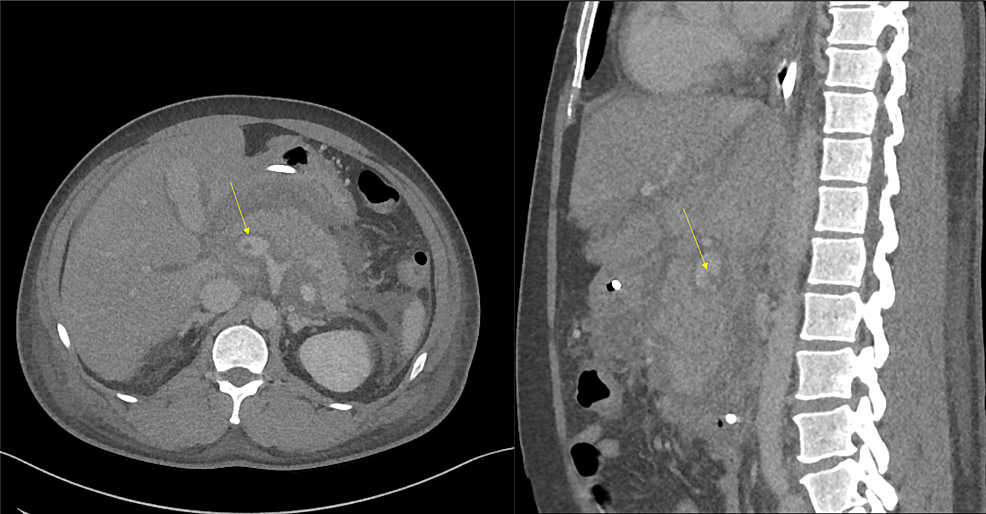

The patient was a 44-year-old male without any significant past medical history who presented to the emergency department (ED) with complaints of severe 10/10 epigastric pain for approximately four hours. The patient described the pain as sharp, stabbing, epigastric abdominal pain that radiated to the back. The examination was notable for generalized abdominal tenderness mostly on the epigastric region without any masses or noted rebound. The patient did not have a history of smoking or alcohol consumption and took no home medications. Initial laboratory workup was significant for white blood cell (WBC) count of 19.2 K/uL (normal range: 4.3-10 K/uL), hematocrit of 50% (normal range: 40-48%), potassium of 5.4 mmol/L (normal range: 3.5-4.9 mmol/L), glucose of 269 mg/dL (normal range: 65-110 mg/dL), hemoglobin A1c of 8.3% (normal range: 0-6%), lipase of 12,405 U/L (normal range: 23-300 U/L), C-reactive protein (CRP) of 18.7 mg/dL (normal range: 0-9 mg/dL), cholesterol of 452 mg/dL (normal range: ≤199 mg/dL), triglyceride of 5,837 mg/dL (normal range ≤149 mg/dL), lactate dehydrogenase (LDH) of 412 U/L (normal range: 140-280 U/L), calcium of 5.9 mg/dL (normal range: 8.2-10.4 mg/dL), total bilirubin of 6.9 mg/dL (normal range: 0.2-1.3 mg/dL), and a calculated Ranson’s score of 8, indicating severe pancreatitis. An abdominal CT scan with contrast revealed non-necrotic pancreatitis with an association of duodenitis (Figure 1).

An ultrasound of the gallbladder was done upon admission, which showed no evidence of biliary stones. The patient was kept nil per os (NPO) and was started on 250 mL/h of lactated Ringer’s solution. The pain was controlled with intravenous hydromorphone, and the patient was transferred to the ICU for close monitoring. After six hours, the abdominal pain worsened, and the patient developed abdominal distension and increased bladder pressure (34 mmHg). A kidney, ureter, and bladder (KUB) X-ray revealed significant gastric distention (Figure 2A). Given the suspicion of abdominal compartment syndrome (ACS), the patient was placed in a supine position and received muscle relaxants. A nasogastric tube (NGT) was inserted and the surgical team was consulted. The patient was managed with these conservative measures, and a follow-up KUB (Figure 2B), bladder pressure, and abdominal examination showed significant abdominal decompression.